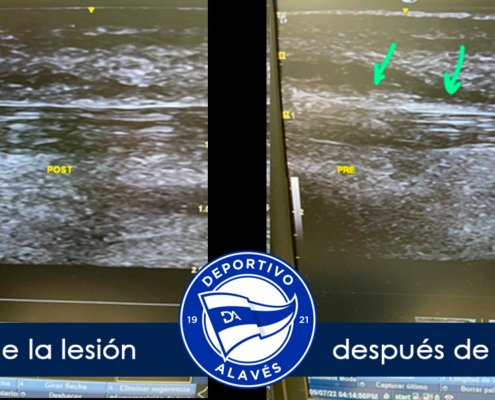

La terapia diamagnética ha revolucionado la manera en que tratamos diversas afecciones, desde lesiones deportivas hasta dolencias crónicas. En esta página, encontrarás una recopilación detallada de casos clínicos de terapia diamagnética, mostrando cómo este tratamiento innovador ha ayudado a nuestros pacientes a mejorar su calidad de vida.

Los casos clínicos de terapia diamagnética que compartimos en esta página evidencian los beneficios tangibles de este tratamiento:

- Alivio del dolor: Mejora inmediata en afecciones musculares y articulares.

- Regeneración rápida de tejidos: Favorece la curación de lesiones.